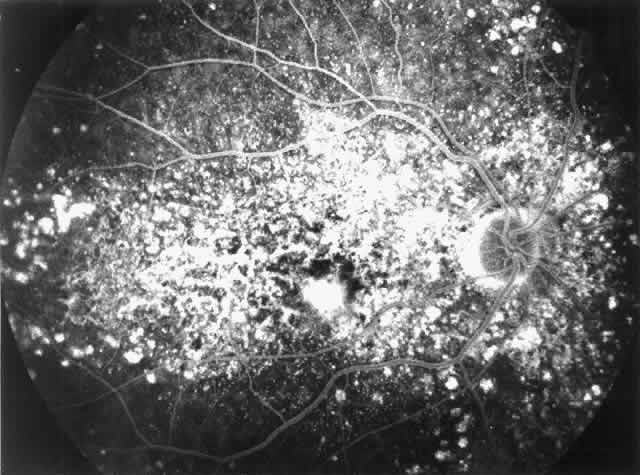

Fig. 7. Fluorescein angiographic changes in a 32-year-old patient with renal signs

of membranoproliferative glomerulonephritis type II since the age

of 9 years. Numerous small and larger drusen-like lesions, atrophic changes, and

a small infrafoveolar subretinal neovascular membrane that

was successfully treated with argon laser coagulation can be seen. (Leys A, Michielsen B, Leys M et al: Subretinal neovascular membranes associated

with chronic membranoproliferative glomerulonephritis type II. Graefes

Arch Clin Exp Ophthalmol 228:499, 1990) Fig. 7. Fluorescein angiographic changes in a 32-year-old patient with renal signs

of membranoproliferative glomerulonephritis type II since the age

of 9 years. Numerous small and larger drusen-like lesions, atrophic changes, and

a small infrafoveolar subretinal neovascular membrane that

was successfully treated with argon laser coagulation can be seen. (Leys A, Michielsen B, Leys M et al: Subretinal neovascular membranes associated

with chronic membranoproliferative glomerulonephritis type II. Graefes

Arch Clin Exp Ophthalmol 228:499, 1990)